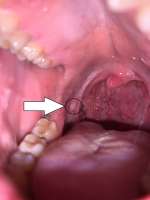

Сап, двач. Три дня назад выскочила такая хуета во рту. Похоже, будто откусил себе часть щеки, и теперь она вниз свалилась. До этого с таким не сталкивался. С утра, когда сильный сушняк (принимаю на ночь Кветиапин), болит, потом не очень, но глотать больно. Что это может быть? На обычный стоматит не похоже.

>>1251820 Действительно, прикусил. Избегать холодной, горячей пищи и напитков. Полощи антисептиком, тип хлоррофиллипт. Через несколько дней пройдет. Будет часто повторяться, нужно будет обратиться к стоматологу. анон-лор-кун

>>1252529 Хуевато сфотографировано, но судя по месту, это гиперкератоз, связанный с прикусом, когда зубы в месте контакта травмируют слизистую. В иедале тебе к стоматологу. >>1253426 Это не болезнь. По крайней мене как правило патологии не находят в самом ухе. Связано с потерей тепла, спазмом сосудов барабанной перепонки, болью. Не вылечить. Утепляйся. Наушники, головные уборы прикрывающие ушные раковины.